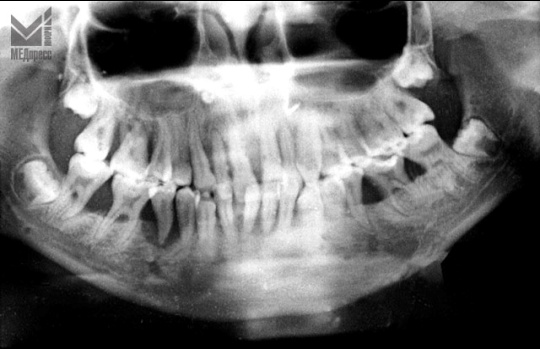

| Рис. 3. Генерализованный неравномерный остеолизис костной ткани альвеолярного отростка. В области 45 зуба остеолизис распространяется до верхушки корня. |